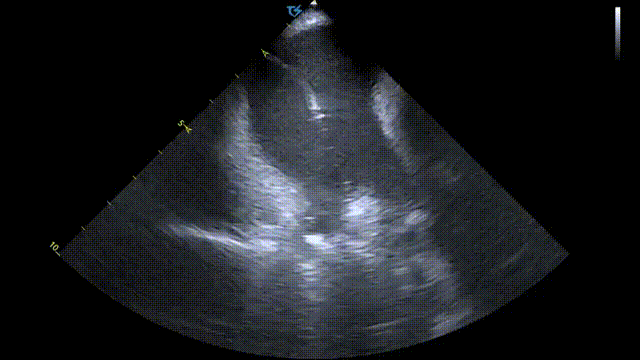

术前ICE左房血栓筛查

术中ICE指引导丝到上腔静脉

ICE直视下进行房间隔穿刺

穿刺后打水确认

LSPV消融:

LSPV口内消融_ICE直视下脉冲导管以网篮形态与肺静脉贴靠

LSPV前庭消融_ICE直视下,显示脉冲导管以花瓣形态与肺静脉贴靠

ICE直视下,CP导管呈现网篮形/花瓣状贴靠在左上肺静脉,并可观察到导管进入肺静脉的深度&贴靠情况

ICE直视下,PFA导管进行左下肺静脉贴靠消融

术前术后心包对比:

术前心包基线扫描

术后心包检查

本次手术是在霆升心腔内超声指导下进行的脉冲消融手术。由于ICE提供的是实时且高清的图像,一方面可以清楚直视房间隔的位置,对于房间隔穿刺有很大的优势,另一方面术中医生可以实时观察到脉冲导管在肺静脉口部及前庭贴壁的情况,并且能实时监测到可能的并发症,如心包积液,从而显著减少了对放射线的需求。两者结合后,ICE指导下脉冲电场消融有望引领房颤消融进入新阶段。